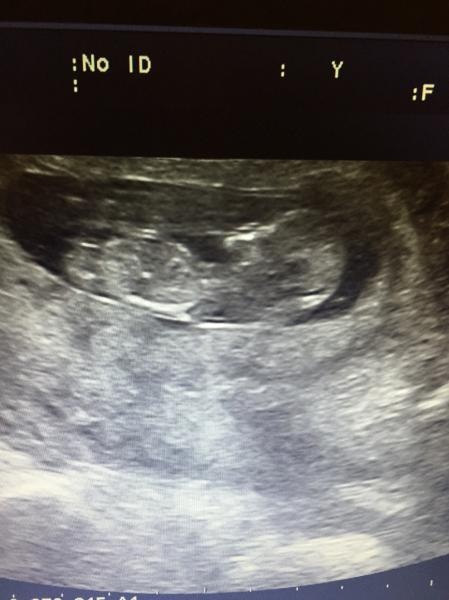

Agge83 skrev 2017-02-22 20:57:46 följande:

Nån som vill gissa!? Drygt 3 veckor kvar till rul :)

Jag gissar på pojke men är osäker.. ser ingen nubbe. Har du någon annan bild?